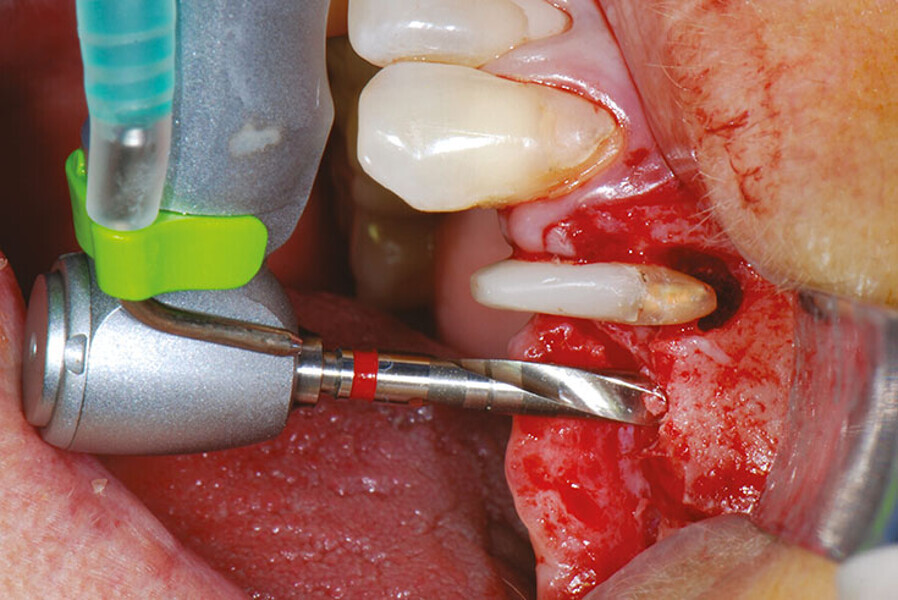

Case report